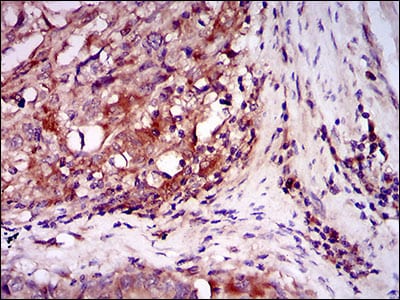

| IHC | 1/200 - 1/1000 | Human,Mouse,Monkey |

**摘要**:研究通过免疫组化分析发现ILK在多种肿瘤中高表达,且其表达水平与患者预后相关。利用ILK抗体阻断实验表明,抑制ILK活性可减少肿瘤侵袭和转移,提示其作为癌症治疗靶点的潜力。

ILK antibodies are essential tools for studying its expression, localization, and function in both physiological and pathological contexts. Overexpression or dysregulation of ILK has been implicated in cancer progression, fibrosis, and cardiovascular diseases, making it a potential therapeutic target. Researchers use ILK-specific antibodies in techniques like Western blotting, immunohistochemistry, and immunofluorescence to assess protein levels in tissues or cultured cells. These antibodies also aid in exploring ILK's role in mechanotransduction and its interaction with binding partners like PINCH and Parvin. Validated ILK antibodies are commercially available, often distinguishing between phosphorylated and total protein forms to study activation states. Their application has advanced understanding of ILK's dual roles as a kinase and scaffolding molecule in development and disease.